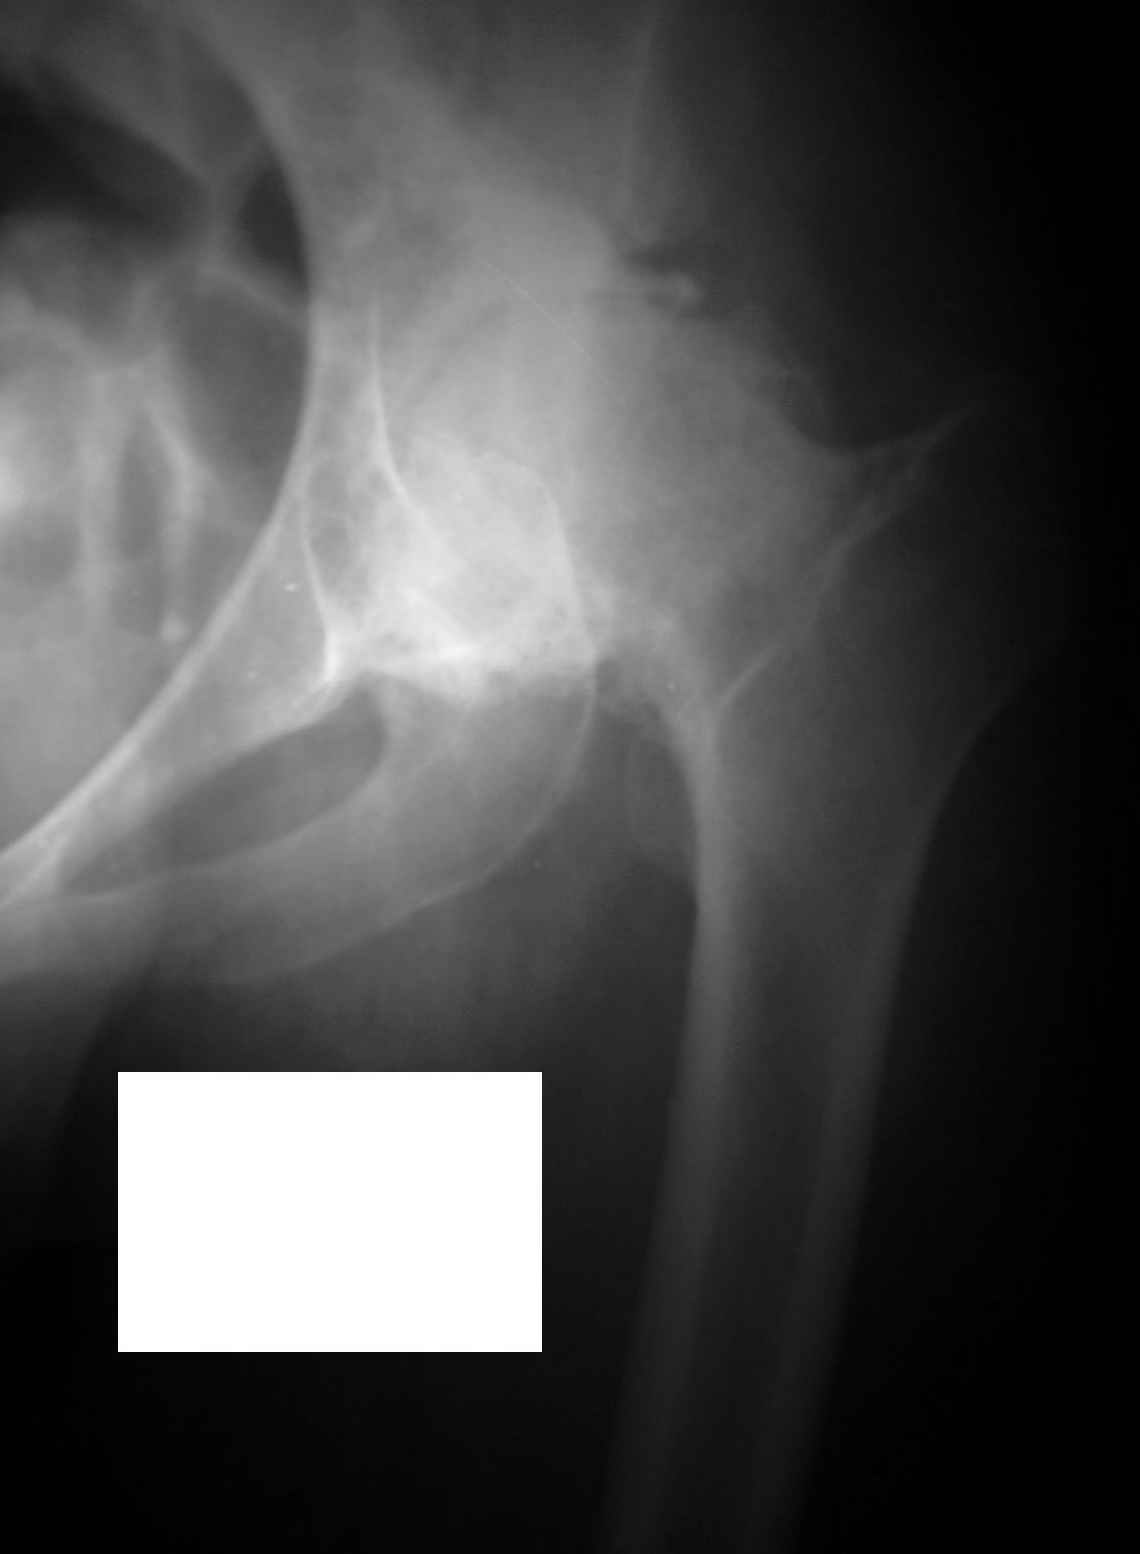

Уважаемые коллеги, во вложении р-граммы 24-летней женщины. Обратилась первично.

Жалобы на боли, ограничение движений, хромоту. Болеет с 14 лет. С её слов, перенесла болезнь Пертеса. Документов нет. Обьективно: выраженнаяприводяще-сгибательная-ротационная контрактура, функциональное укорочение - 5см.Вопросы:-какая система, на ваш взгляд, наиболее оптимальна для протезтрования?-возможно-ли выполнить протезирование в один этап,восстановив длину и функцию конечности?Спасибо.Ринат. г.Уфа

Судя по седловидной деформации головки бедренной кости можно предположить, что больная перенесла болезнь Пертеса.

Коллега, посмотрите на состояние головки и величину укорочения.

Извините, Анатолий, головка не выглядит потерянной, укорочение 5 см из-за порочного положения. Подход у молодой женщины я бы выбрал в зависимости от мобильности сустава.

На ригидном суставе межвертельная остеотомия для женщины мало привлекательна, но при гипомобильности, а тем более мобильности сустава вполне пригодна. И эффект от операции мы наблюдаем больше 10 лет и для последующего эндопротезирования трудности не велики, если остеотомию правильно спланировать и выполнить (проксимальный отдел бедра после остеотомии должен соответствовать нормальной анатомической геометрии). Привожу, что под рукой - Ртг 1997 ( даме 27 лет) и 2004 года. А моделей эндопротезов бесцементной фиксации для такой рентгеноантомической формы коксартроза действительно достаточно.

По представленным раздельным Рг граммам сложно судить о причине столь значительного укорочения, вполне вероятно что причина комплексная:

1 разрушение головки

2 разрушение впадины

3 поясничный сколиоз

По моему мнению, у Вашей пациентки выявлены последствия эпифизеолаза (slipped capital femoral epiphysis).В данный момент у нее наблюдаются признаки коксита (laminar coxitis), что является наиболее тяжелым осложнением в таких случаях. Я не мог бы предложить другого метода лечения, кроме эндопротезирования сустава. Удлиннить бедро на 5 см. можно во время операции без особых затруднений с помощью тенотомий.